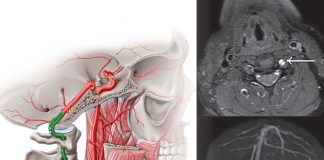

Vertebral Arter Diseksiyonu

Vertebral arter diseksiyonu (VAD), posterior iskemik inmeye yol açabilen, genel popülasyonda nadir görülen ancak hayatı tehdit eden bir akut serebrovasküler olaydır. Belirtileri ve bulguları...